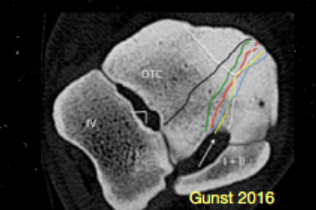

Three normal lucencies visible on a DLPMO rad

1) Synovial fossa in the intertrochlear groove of the talus proximally

2) Sinus tarsi - between talus and calcaneus platarolaterally

3) Tarsal canal between central/third and fourth tarsal bones